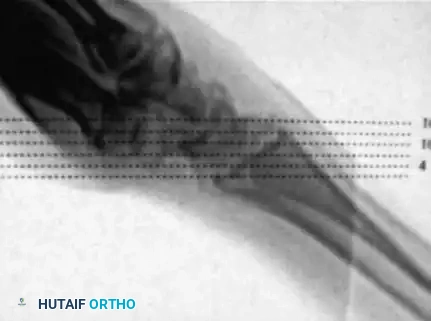

For true sagittal plane images of the scaphoid, the patient's forearm is held pronated, and the hand lies flat on the CT table. The forearm crosses the gantry at an angle of approximately 45 degrees, roughly in line with the abducted thumb metacarpal.

Scout images are obtained to confirm appropriate orientation and to ensure that the entire scaphoid is captured within the imaging field. Sections are obtained at 1-mm intervals to maximize resolution.

For true coronal plane images, the forearm is positioned in neutral rotation.

Scout images demonstrate the alignment of the wrist through the gantry of the scanner, ensuring the imaging plane is parallel to the long axis of the scaphoid.